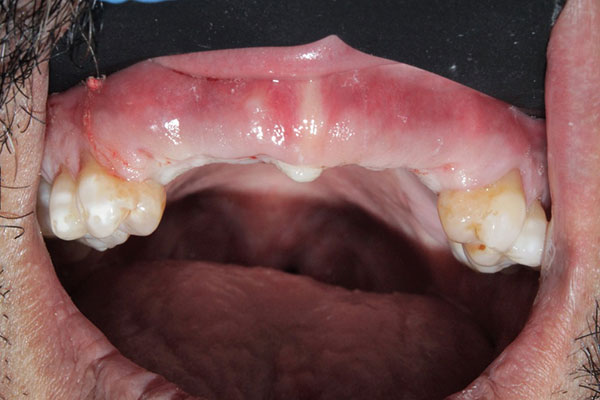

Here is a picture of the patient after surgery. As you can tell there is very little swelling or annoying stitching. Healing time is enhanced, making your implant experience a walk in the park for many patients and doctors alike!